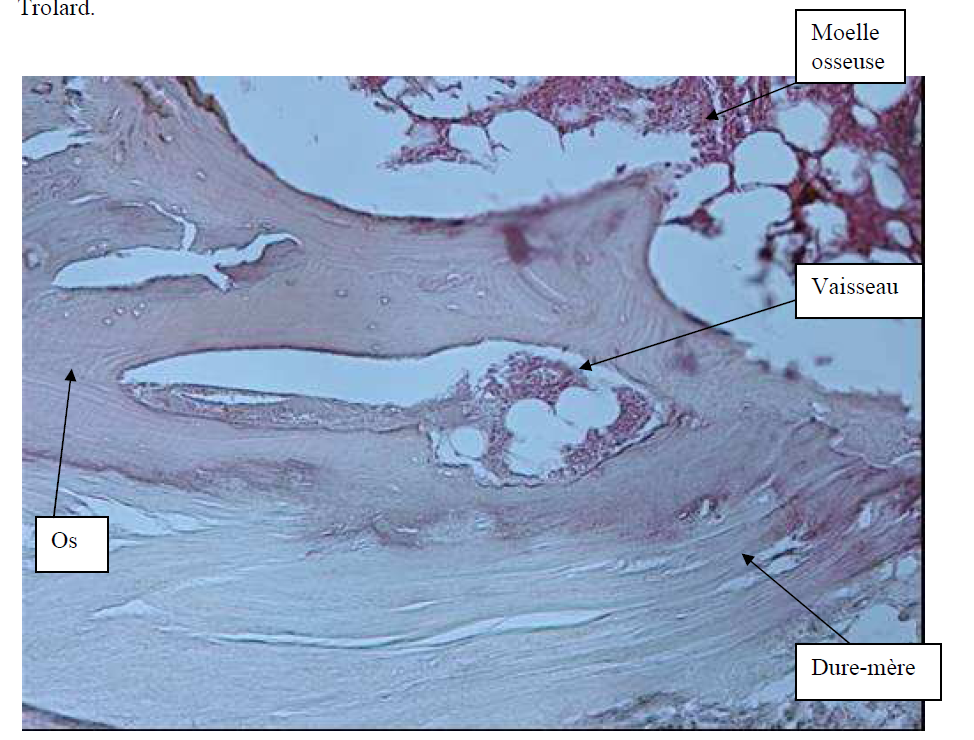

Photo INSERTIONS DE LA DURE-MERE SUR LE RACHIS Une anatomie redécouverte 32